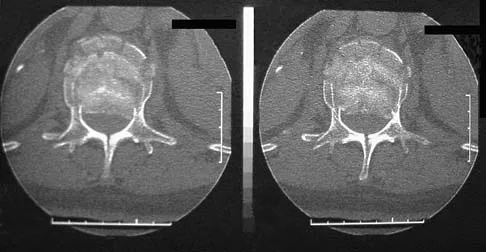

An otherwise healthy 45-year-old woman reports the onset of severe right leg pain. Figure 20a shows an axial MRI scan of the L4-5 level, and Figure 20b shows a sagittal view with the arrow at the L4-5 level. What nerve root is the most likely source of her pain?

The scans show a disk herniation in the far lateral region of the disk. In particular, the sagittal view shows the herniation adjacent to the exiting L4 nerve root. Disk herniations in this area that cause symptoms are more likely to compress the nerve exiting at the same level rather than the next most caudal level. McCulloch JA: Microdiscectomy, in Frymoyer JW (ed): The Adult Spine: Principles and Practice. New York, NY, Raven Press, 1991, vol 2, pp 1765-1783.